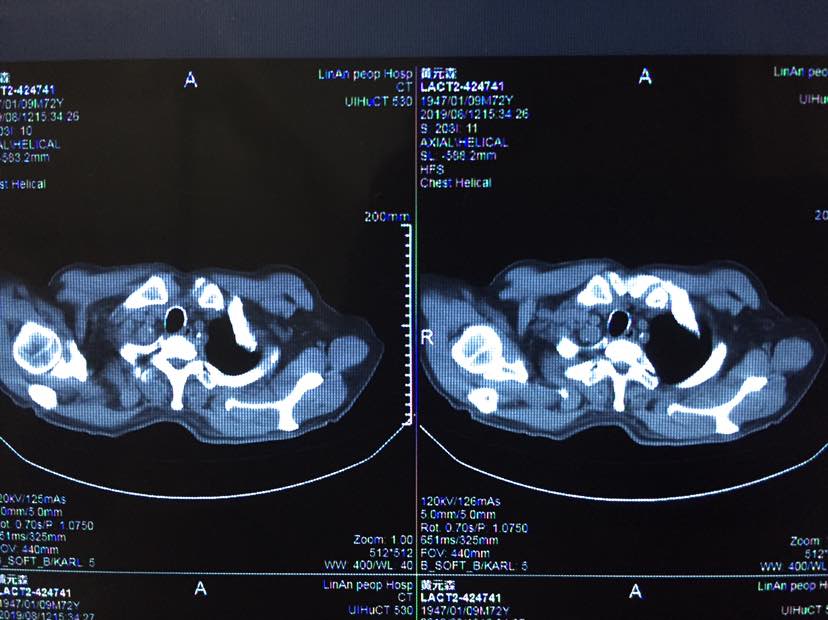

2019年8月9日,父亲接受第十三针k药的治疗,注射之前进行了全面的检查,生化、肿瘤标的物、b超、ct等结果显示,父亲目前状况非常正常,除了肺内胸膜有阴影不能确认活性以外,其他病灶都消失了,父亲现在体感很好,无任何胸痛胸闷气短等症状,依然与常人无异,持续稳定中,希望这种状况能持续的长久一些!也祝各位病友好运长久!